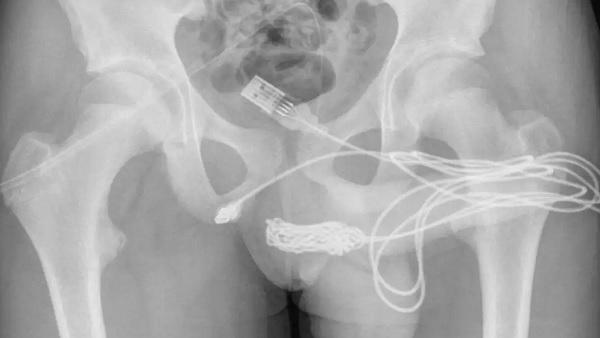

नई दिल्ली, 07 सितंबर: एक बेहद ही अजीबो-गरीब मामला सामने आया है। इसपर विश्वास करना थोड़ी मुश्किल हो सकती है, पर सत्य है। एक किशोर अपने प्राइवेट पार्ट के अंदरूनी हिस्सों को यूएसबी केबल से मापने की कोशिश कर रहा था। इस बीच उसके लिंग में यूएसबी केबल फंस गया। इससे उसे काफी परेशानी होनी लगी। जब उसे अस्पताल पहुंचाया गया तो डॉक्टर भी हैरान हो गए।

बता दें कि इस बच्चे ने प्रयोग के दौरान अपने प्राइवेट को नाप रहा था। इसी बीच उसके अंदर केबल फंस गया। निजी अंगों के अंदरूनी हिस्सों को मापने का प्रयास करने के दौरान वह फंस गया और केबल में गांठों और उलझनों के कारण लड़के के पेशाब में खून आने लगा।

साइंस डायरेक्ट की रिपोर्ट में डॉक्टरों ने लिखा कि यूएसबी वायर के दो डिस्टल पोर्ट बाहरी यूरेथ्रल मीटस से बाहर निकलते हुए पाए गए, जबकि नॉटेड वायर का मध्य भाग यूरिनल के भीतर फंसा रहा।

चिकित्सकों ने कहा कि तार के दोनों सिरों को बाहरी मूत्रमार्ग के माध्यम से सफलतापूर्वक बाहर निकाला गया। लड़का ठीक हो गया और उसे छुट्टी दे दी गई। चेतावनी दी कि मूत्रमार्ग में वस्तुओं को डालने से पेशाब करते समय दर्द हो सकता है।